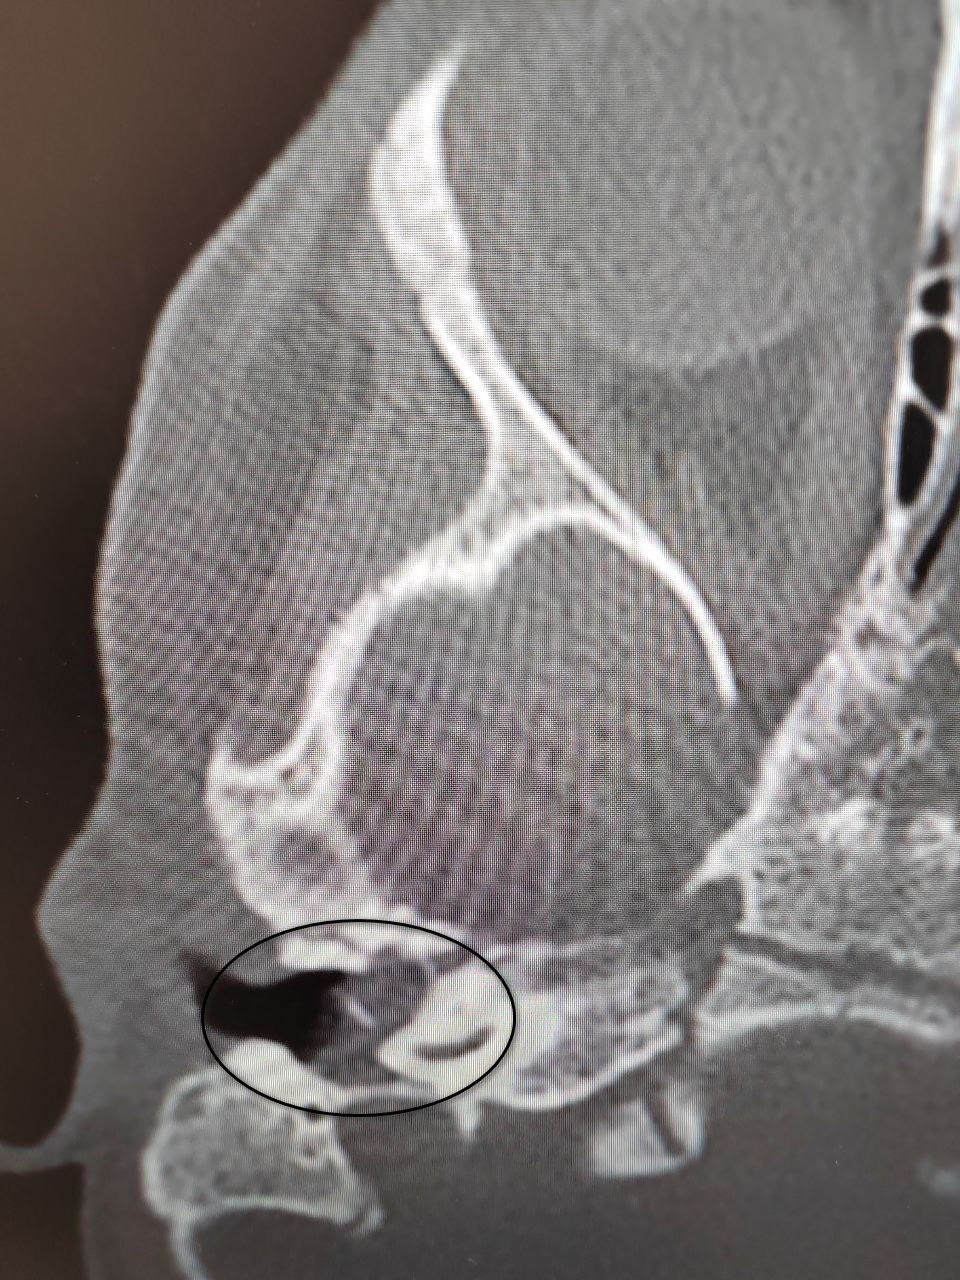

У ребенка все началось в ОРВИ, после которой появились боли в ухе. Затем ситуация осложнилась парезом лицевого нерва, который характеризуется слабостью мимических мышц. В результате обследования специалисты подтвердили диагноз «врожденная холестеатома».

Тогда медики решили провести сложную операцию — аттико-антротомию с тимпанопластикой справа. Заведующий отделением удалил холестеатому, провел декомпрессию лицевого нерва и восстановил механизм звукопроведения